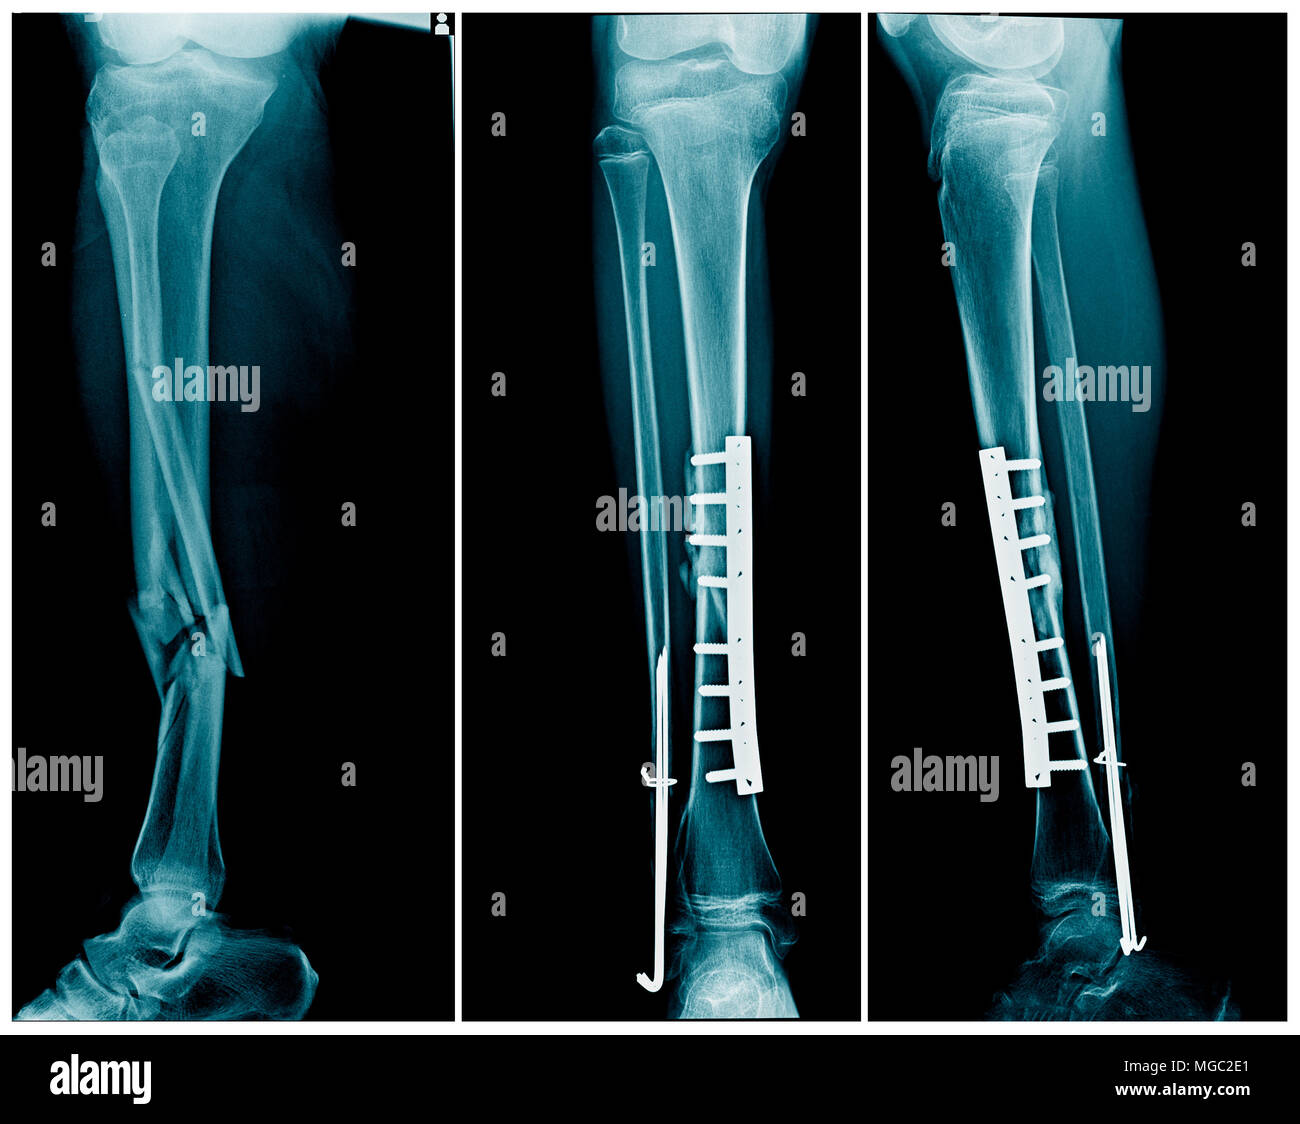

Internal fixation involves the surgical placement of screws, plates, rods, or wires directly onto or within the bone to stabilize the fracture. This technique is often used for more severe fractures, such as displaced or unstable fractures.

Internal fixation refers to the method of physically reconnecting the bones. This might involve special screws, plates, rods, wires, or nails that the surgeon places inside the bones to fix them in the correct place. This prevents the bones from healing abnormally. The entire operation usually takes place while you are asleep under general anesthesia.

Screws and plates are used to hold bone fragments together. Plates are attached to the surface of the bone with screws to maintain alignment.

These are metal rods inserted into the medullary canal of long bones, such as the femur or tibia. They provide stability along the length of the bone.